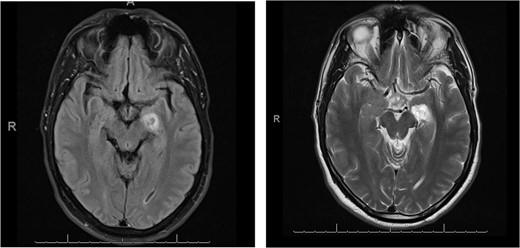

A 40-year-old man subjected to the outpatient care of our hospital for many years with the diagnosis of temporal epilepsy with complex partial seizures. After a long period free of seizures came in 2019 to a recurrence with episodes of focal epileptic seizures. The brain imaging with cranial magnetic resonance tomography (MRT) revealed a new lesion on the left hippocampus. The patient underwent regularly follow-ups in our outpatient clinic and the lesion has been shown stable until the last brain imaging in May 2022. The lesion has been changed morphologically and presented larger in size, with an increase in contrast enhancement. The lesion has appeared with a total mass of 8 × 14 × 15 mm, hypointense, surrounded by a peripheral hyperintense area, in the Flair sequence, Fig. 1. At that moment the patient complained intermittent dizziness and headache. He was otherwise alert, oriented with glasgow coma scale (GCS) 15/15. There was any cranial nerve palsy or neurological deficit of the extremities. The gait presented smooth and coordinate.

Flair sequence showing the lesion in the left amygdala as hypointense with surrounding hyperintense edema (links). T2-weighted imaging presenting the lesion hyperintense in the left amygdala (right).